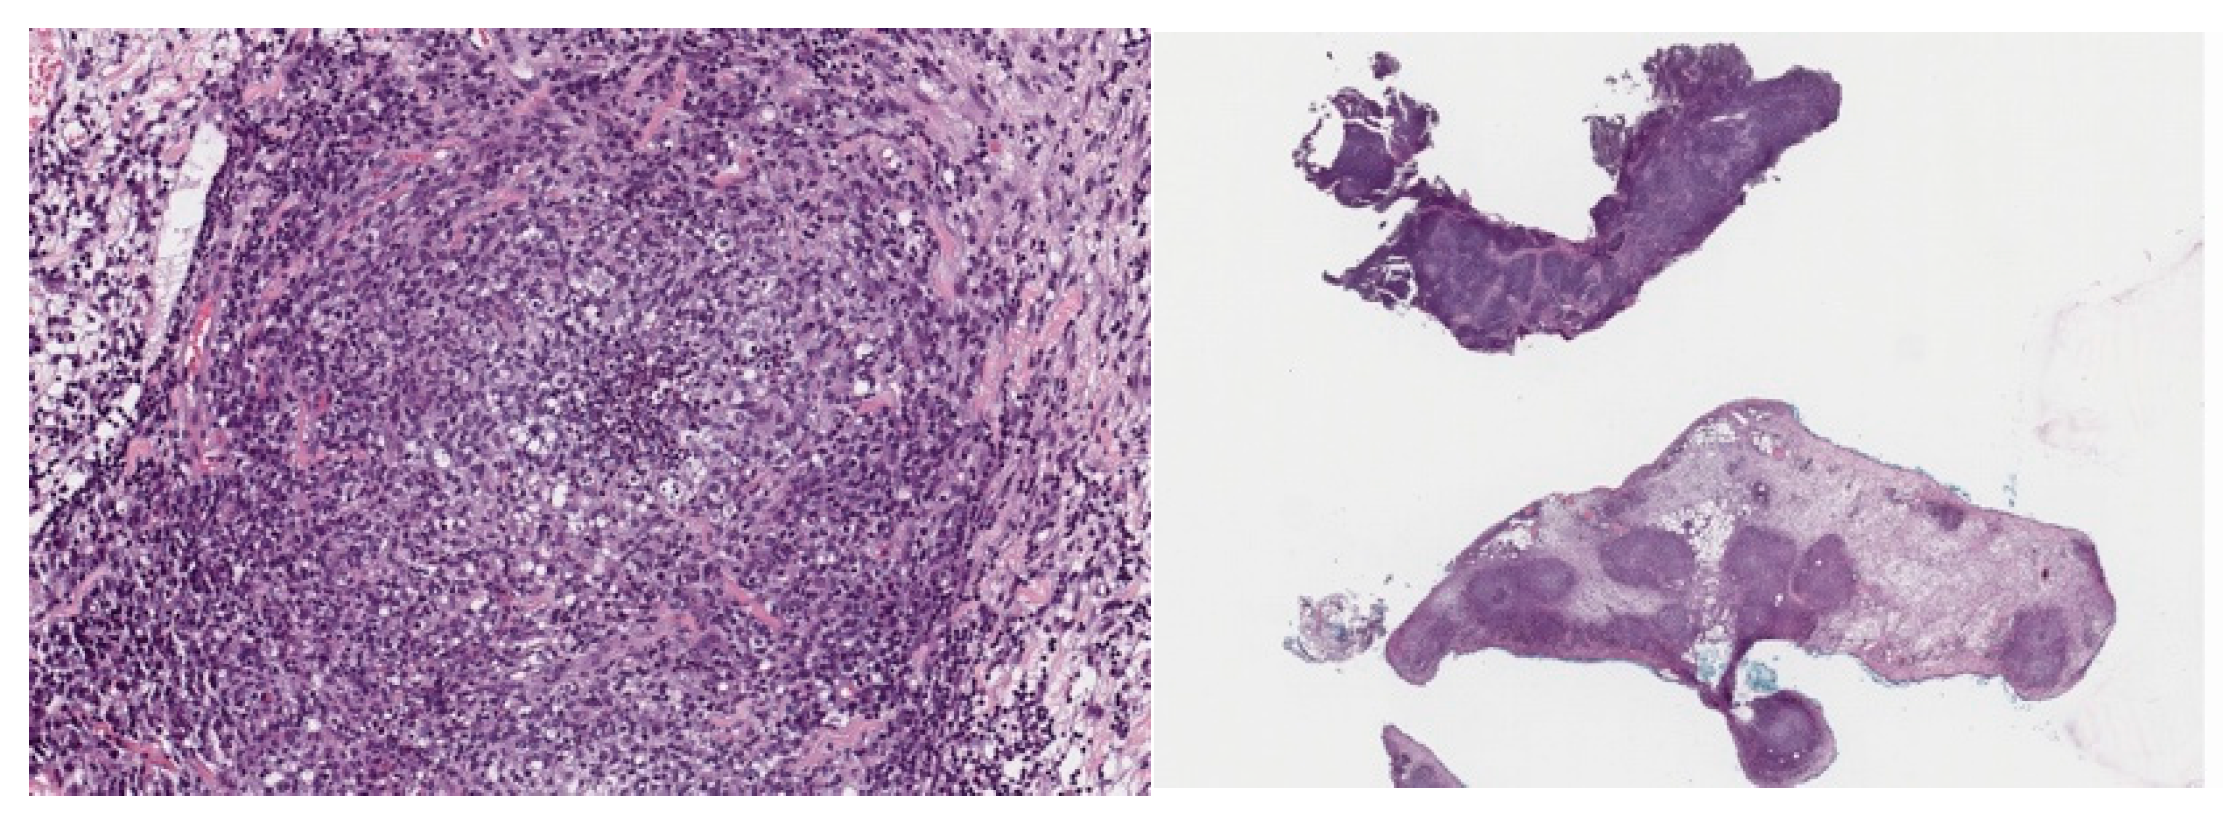

An 8-month-old male ferret presented to the clinic lethargic with diarrhea, loss of appetite and weight loss. The blood chemistry and CBC showed low total protein levels with low albumin (1.5 g/dL) and normal globulins, indicating a low A/G ratio (0.5). The analysis also showed low HGB and HCT but normal white blood cell count (Table 1). A palpable mass was discovered in the abdominal region. A biopsy of the abdominal mass and the mesenteric lymph node was collected due to its enlargement. The histopathology analysis revealed the lymph node was distorted by pyogranulomatous inflammation with no detectable microorganisms present (Figure 1). Pyogranulomatous lymphadenitis in the ferret was described as a concern for FSCD. The veterinarian performed surgery to remove the mass and administered antibiotics and dexamethasone.

Figure 1.

Histopathology images of two samples obtained from the mesenteric lymph nodes biopsied.